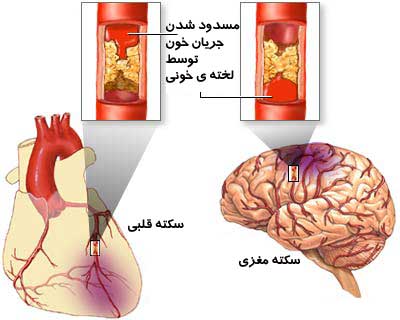

دلیل سکته قلبی

سکته قلبی و سکته مغزی در یک نقطه مشترک هستند ولی پدیده های کاملا” جدا هستند . نقطه مشترک این…

علت بروز سکته قلبی

سکته به معنی حادثه است. سکته قلبی به معنی حمله قلبی و علتش بسته شدن و انسداد رگهای خون دهنده قلب…